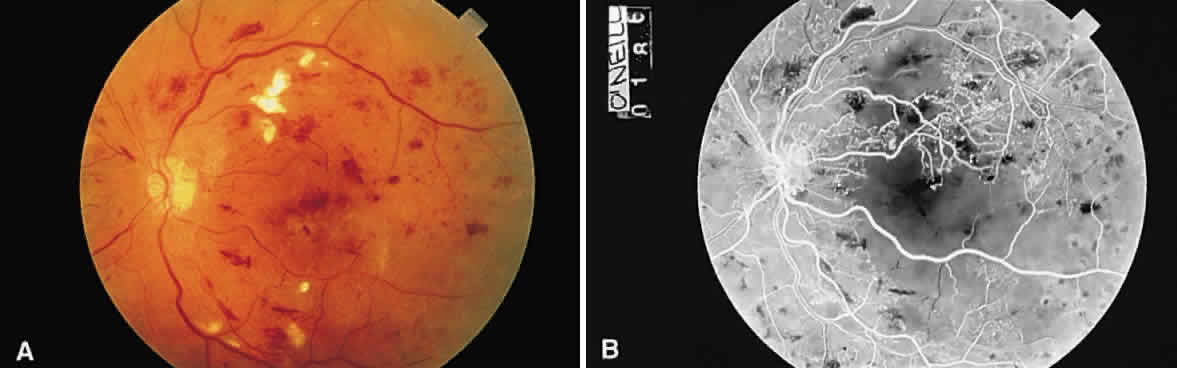

Cotton-wool spots are observed mainly in the posterior pole of the retina (Fig.23) The reason for this geographic restriction is not clear. Occlusion of the most superficial radially oriented peripapillary capillaries (confined in distribution to the posterior pole) has been implicated in the pathogenesis of cotton-wool spots.9 It is also possible that nerve fiber infarcts in the periphery are not visualized because there is insufficient inspissated axoplasmic material in this location.

Fig. 23. Multiple cotton-wool spots along with retinal hemorrhages in a superior temporal branch retinal vein occlusion.

The orientation of the processes of retinal cells deep to the nerve fiber layer is perpendicular to the plane of the internal limiting membrane. Therefore, hemorrhages in the deeper (or outermost) retinal layer are oriented in a cylindrical column. The ophthalmoscopist views a cross-section of this column (the cylinder end-on) and sees a dot or blot hemorrhage (see Fig. 23).